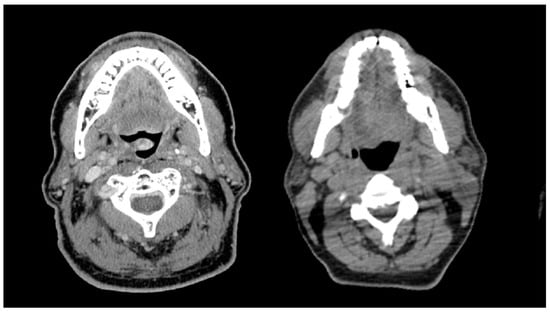

Computed tomography (CT) scans were obtained for all patients at the time of radiation simulation for treatment planning purposes. Body Mass Index (BMI) was calculated using the patient’s weight in kilograms divided by their height in meters squared. Muscle composition was assessed using three different skeletal muscle measures: skeletal muscle index (SMI), skeletal muscle density (SMD), and skeletal muscle gauge (SMG). Skeletal muscle measurements were obtained from treatment planning CT scans using National Institutes of Health (NIH) ImageJ software. All skeletal muscle contouring was performed by a single researcher who was not aware of patient outcomes (R.G.G). An example from this dataset is shown in Figure 1.

Figure 1. A representative case example of a 54-year-old man with an HPV-positive oropharynx cancer. A single axial CT slice is taken at the C3 vertebral body level with contours of the sternocleidomastoid and paravertebral muscles delineated in turquoise. Skeletal muscle was defined as −29 to +150 Hounsfield Units (HUs), and the total cross-sectional area (CSA) was computed automatically within the contoured perimeters.

The presence of sarcopenia was assessed using SMI, a validated method using CT-based measurements to calculate skeletal muscle mass [18,19]. SMI was calculated as previously described by Swartz et al. using a single axial CT slice at the C3 vertebral body level [19]. SMD was calculated using the mean attenuation within the same contoured perimeter. SMI and SMD thresholds were made consistent with thresholds that have been associated with increased mortality in a large cohort of cancer patients [20]. SMG was calculated as the product of SMI and SMD as described by Weinberg et al. [21]. Patients were dichotomized around the median in the overall cohort into low and high SMG groups for data analysis.